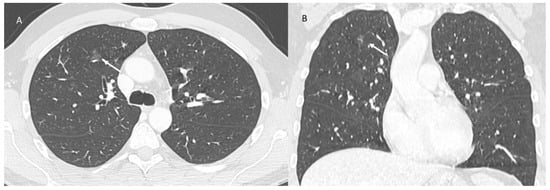

2. Immune Checkpoint Inhibitor-Related Pneumonitis

| Type of Pneumonia | Lung Involvement | CT-Patter |

|---|---|---|

| COVID-19 Pneumonia | Diffuse (related to the phase of disease) | ground-glass opacity, crazy-paving pattern, consolidative opacities, interlobular septal thickening (according to the phase of disease) |

| RRR-Related Vaccine | Target Area | Consolidative opacities |

| Pulmonary lymphangitis carcinomatosa | Diffuse (related to the phase of disease) | Irregularly interlobular septal thickening, smooth (early stage), or nodular thickening (late development), ground-glass opacity, pleural effusions. |

| ICI-Related Pneumonitis | Diffuse (related to the phase of disease) | ground-glass and reticular opacities, consolidative opacities, interlobular septal thickening, “crazy-paving” pattern |